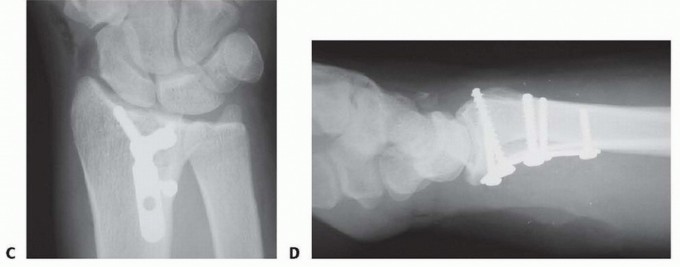

TECH FIG 5 • Volar rim fixation with small fragment plate. A,B. Shear fracture of volar rim with volar instability pattern. C,D. Fixation with small fragment plate.